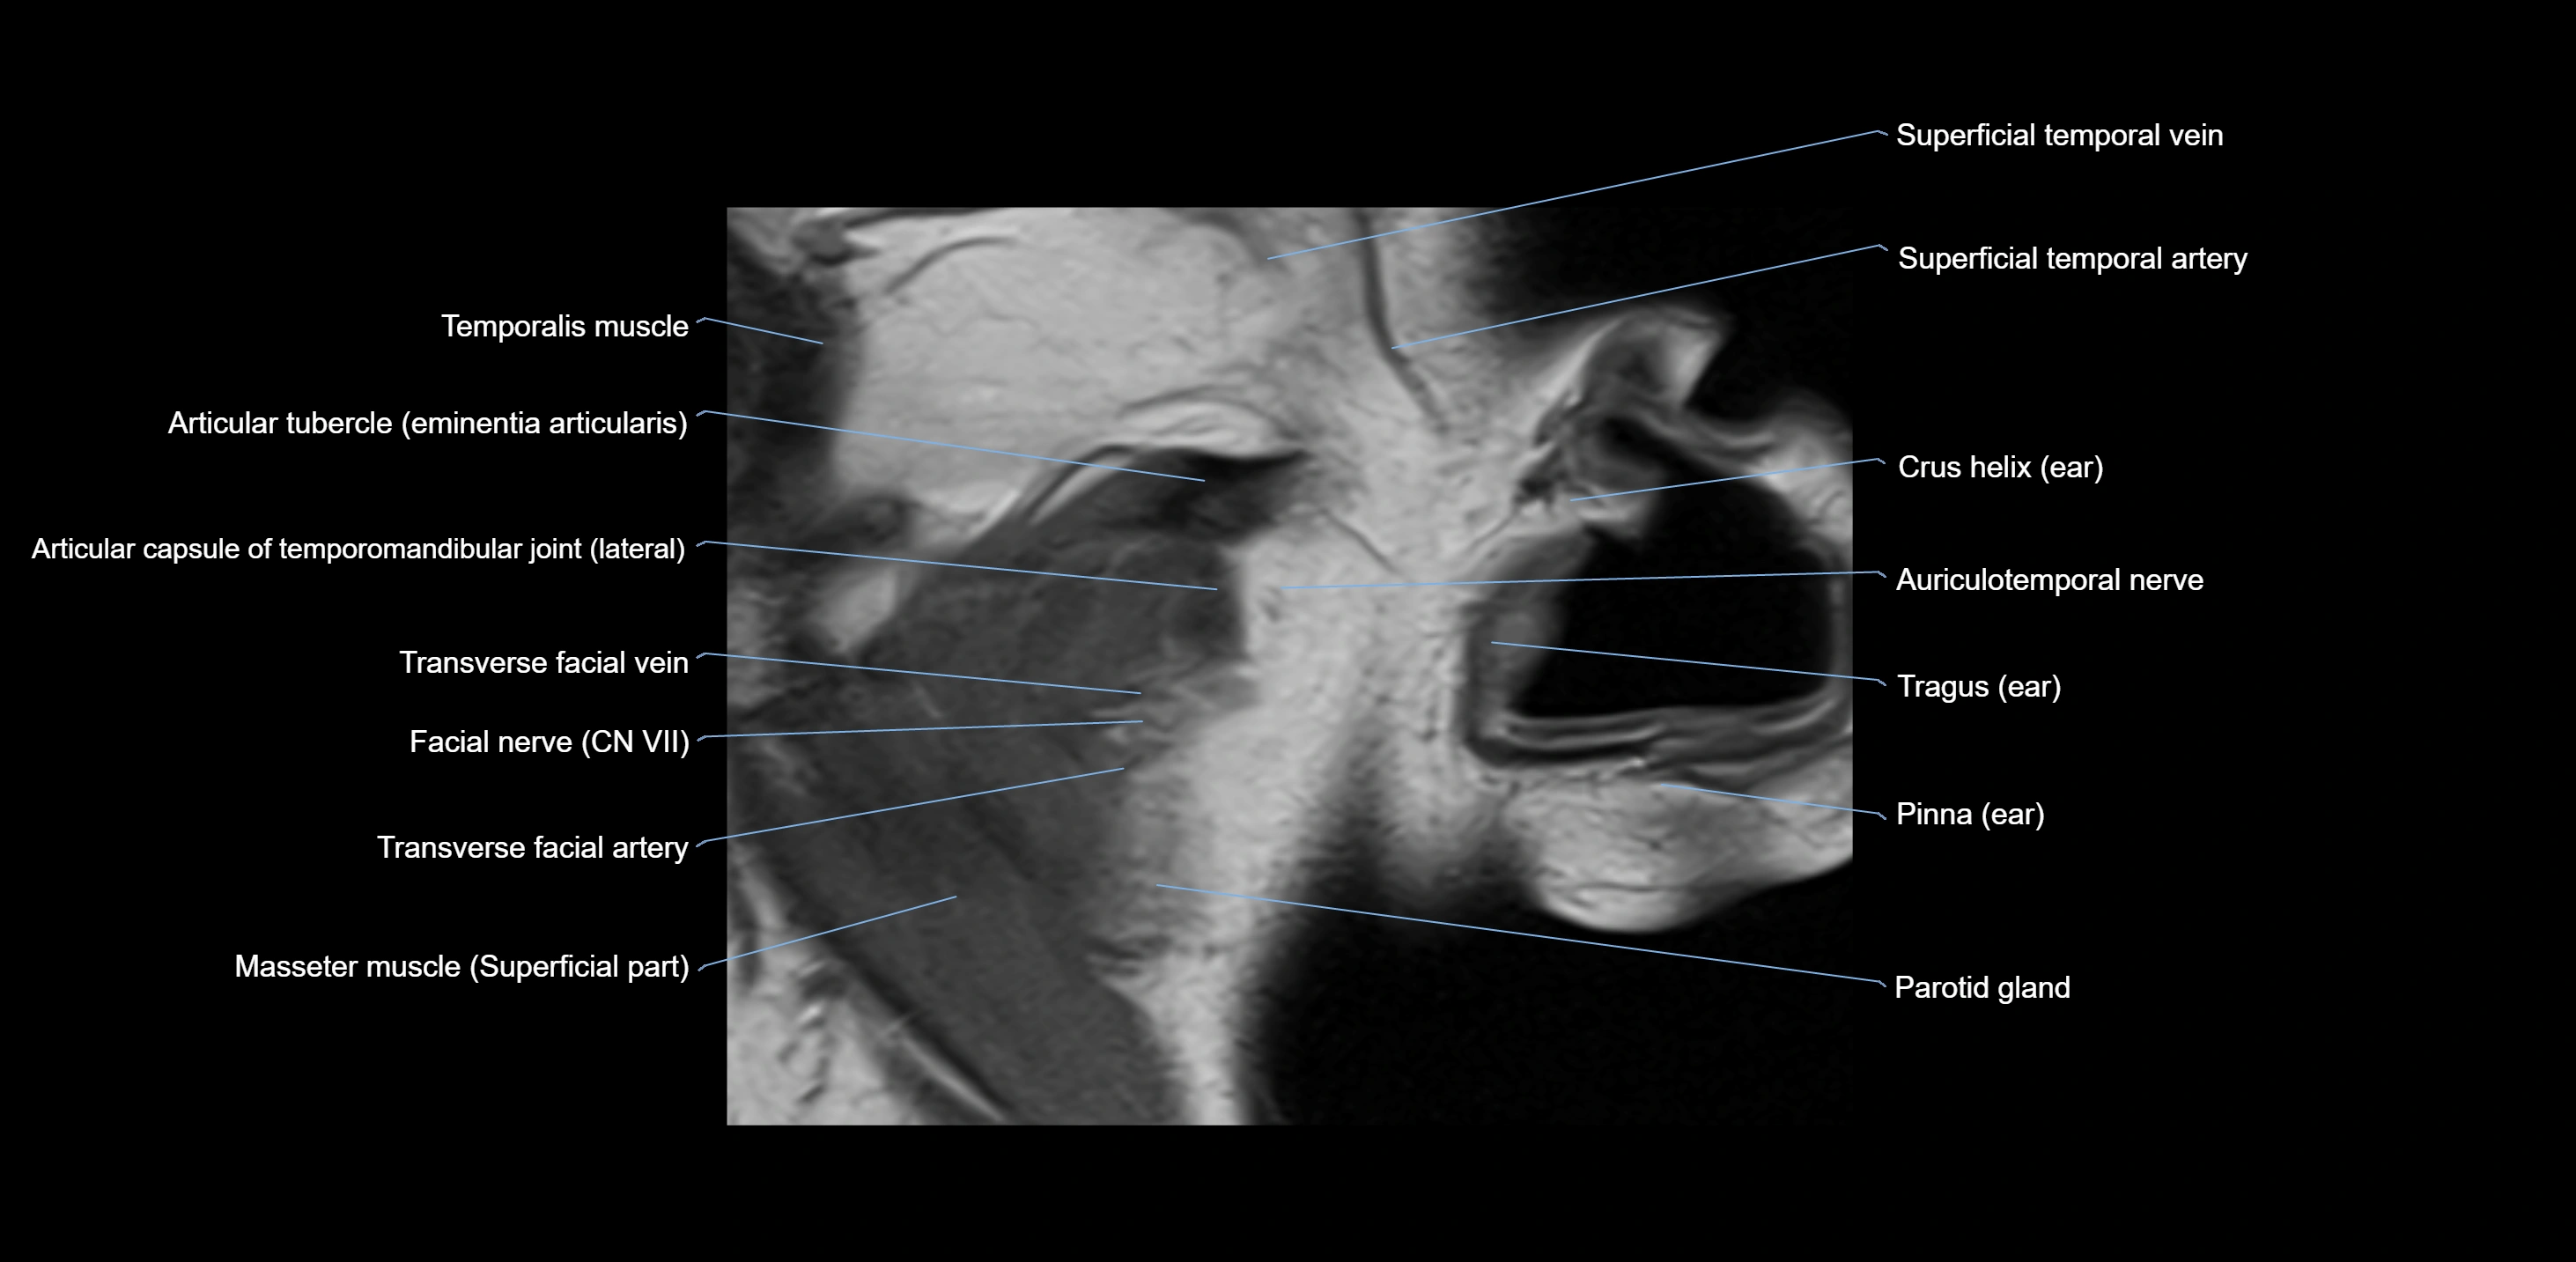

MRI appearance

T1-weighted images:

• Cortical bone: Low signal intensity

• Cancellous marrow: Intermediate to high signal depending on fatty content

• Teeth: Signal void structures

• Adjacent soft tissues: Normal gingiva and oral mucosa signal

T2-weighted images:

• Cortical bone and teeth: Low signal

• Marrow: Intermediate signal